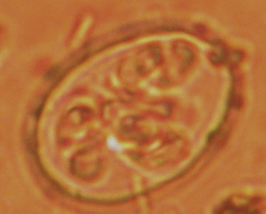

Eimera oocyst